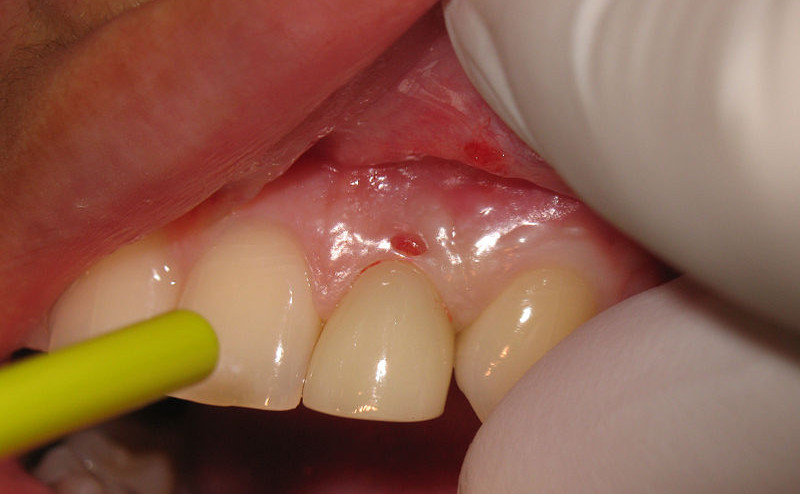

La parodontologia si occupa di trattare i problemi dei tessuti molli, come le gengive e i legamenti periodontali, e i tessuti duri (tessuto osseo alveolare), che garantiscono la stabilità del dente nell'arcata alveolare.

Più in generale, si occupa delle classiche malattie del parodonto, come la piorrea, le parodontiti e le gengiviti.

La causa principale di queste malattie è l'accumulo di batteri tra gengiva e dente.

Non sempre provocano dolore, ma causano gonfiori, arrossamenti o in certi casi sanguinamenti delle gengive. In

alcuni casi si può avere la percezione di denti non stabili e "dondolanti".

Le cure per rimediare a questi problemi variano a seconda dei casi. Con le moderne tecnologie riusciamo oggi ad ottenere risultati impensabili fino a pochi anni fa!